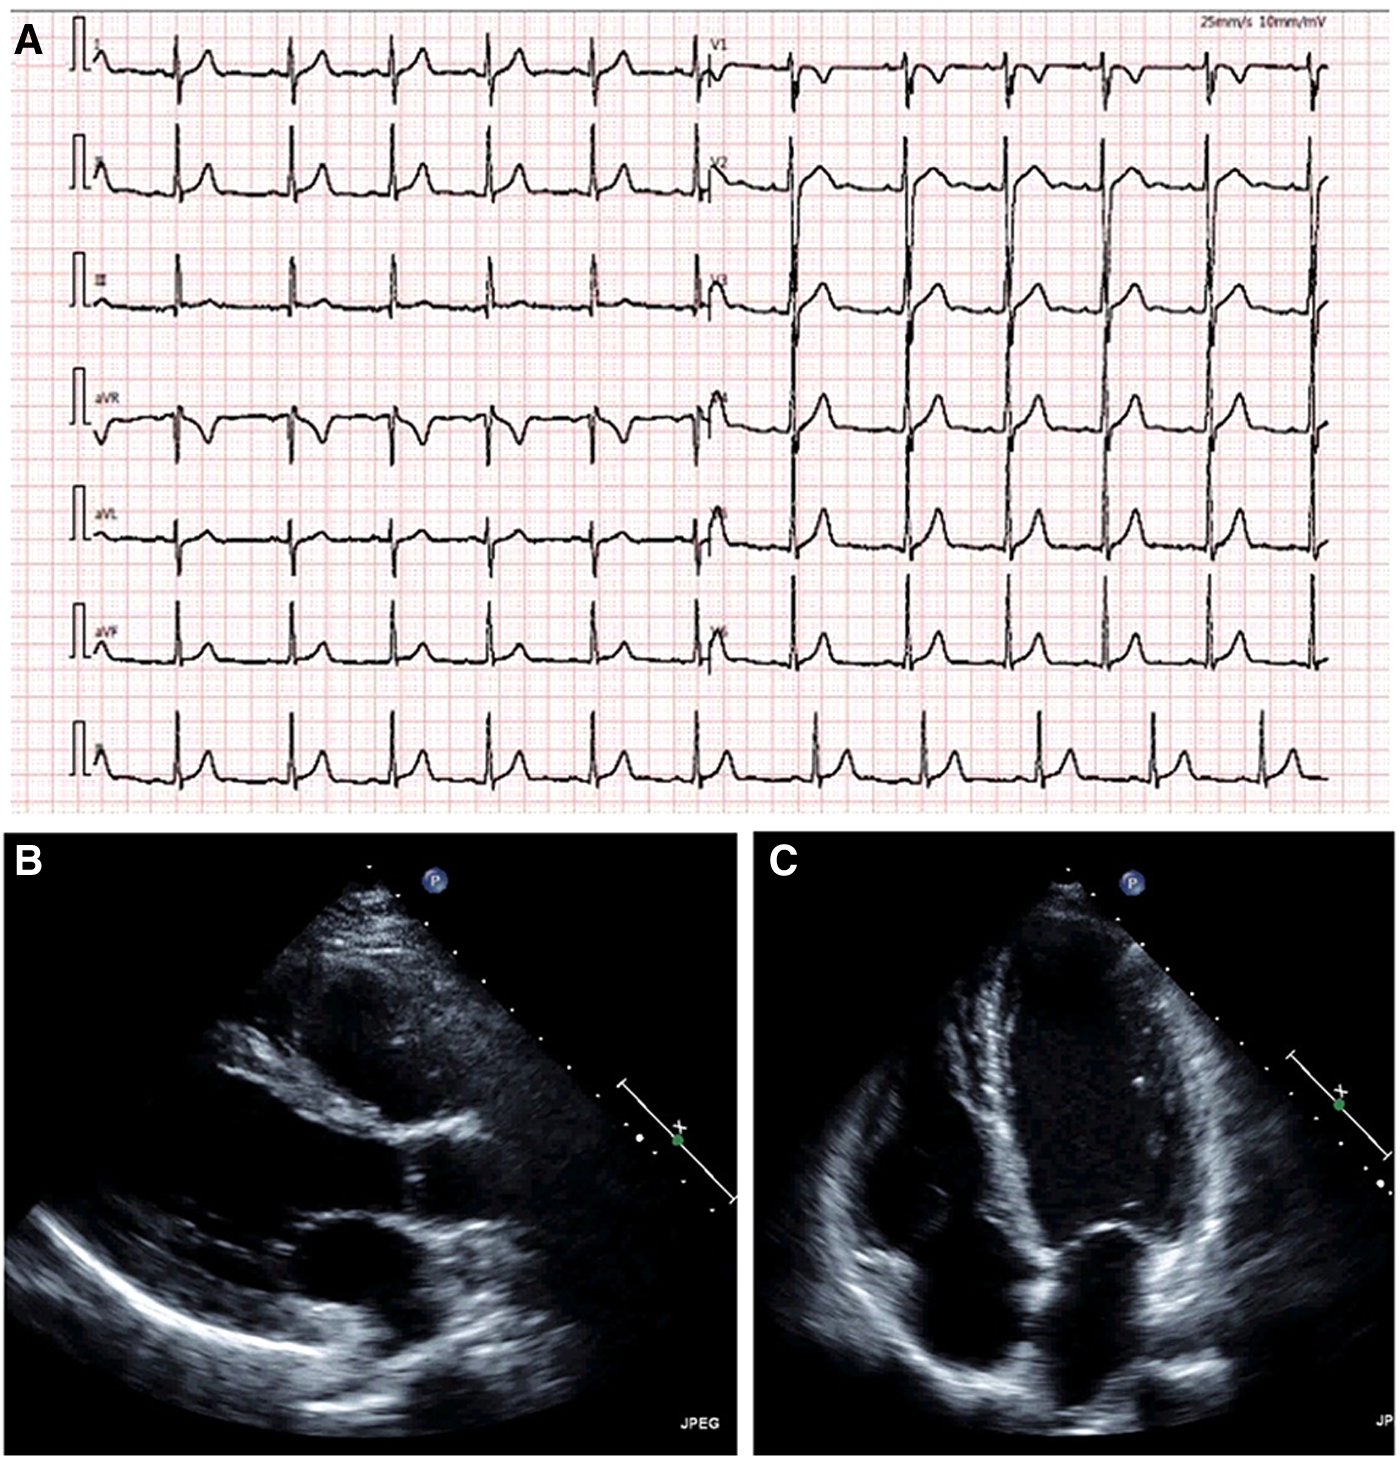

A 14-year-old adolescent presented to our hospital with a complaint of syncope during exercise (playing basketball). He reported feelings of dizziness, sweating, and blackness before fainting. He denied having chest pain or abnormalities in limb movement before and after the occurrence of the episodes. He suffered from two similar episodes in the preceding 2 years while playing basketball and while running. He denied having a family history of coronary artery disease, cardiomyopathy, hypertension, and diabetes. He was diagnosed as experiencing a vagal syncope because of a positive tilt test result a year ago in a local hospital. However, a review of his previous medical records did not reveal any abnormalities. A physical examination on admission revealed normal levels of blood pressure (120/60 mmHg), heart rate (78 beats/min), respiratory rate (18/min), and oxygen saturation of 99% (room air). Cardiac and pulmonary examinations showed normal heart sounds without murmurs and with clear lungs. Laboratory test results indicated normal levels of blood glucose, high-sensitivity troponin, CK-MB, N-terminal B-type natriuretic peptide (NT-proBNP), D-dimer, CBC w/diff, and CMP. The renal and hepatic functions were within normal limits. The baseline ECG displayed sinus rhythm (HR = 78 bpm) without significant abnormalities (Figure 1A). Transthoracic echocardiography (TTE) showed normal cardiac structure and function (Figure 1B). To further investigate the possible reason for syncope, coronary CTA was performed, which revealed an anomalous origin of the LCA originating from the left side of the right sinus of Valsalva and ran between the aorta and the pulmonary artery with an intra-arterial wall course of approximately 20 mm in length (Figure 2A). To clarify whether the anomalous origin of the LCA was the real reason for syncope, we performed CT-FFR on all coronary branches at rest, which revealed an abnormal FFR of the left anterior descending artery (LAD, 0.79) but a roughly normal FFR of the left circumflex artery (LCX, 0.84) and the right coronary artery (RCA, 0.90) (Figure 2B). CT-FFR is a physiologic simulation technique that models coronary flow from routine coronary CTA. To evaluate lesion-specific ischemia, CT-FFR is measured 2 cm distal to a stenotic lesion. A CT-FFR value >0.8 is considered normal, values between 0.76 and 0.8 denote a borderline condition, and a value of 0.75 or less represents an abnormal condition. Since CT-FFR of the LAD was lower than normal at rest, we reasoned that it should be even lower during physical exercise. The cardiac team concluded that the AAOCA was the reason behind the patient’s syncope, following which a surgical correction with a modified unroofing procedure was performed. One week after surgery, repeat CT-FFR was performed to evaluate the effectiveness of the corrective surgery, and the result showed a successful revascularization of the LCA (Figure 3A) and a significantly improved LAD flow with CT-FFR 0.91 (Figure 3B). CT-FFR of the LCX (0.91) and RCA (0.88) remained within normal limits. The patient was discharged 10 days after surgery and followed up on an outpatient basis. He soon resumed his normal activities and had no recurrence of syncope.

Figure 1

Admission electrocardiogram shows sinus arrhythmia without significant abnormalities. (A) Echocardiography shows normal cardiac structure and function (B, C). (B) parasternal long-axis view; and (C) apical four-chamber view.